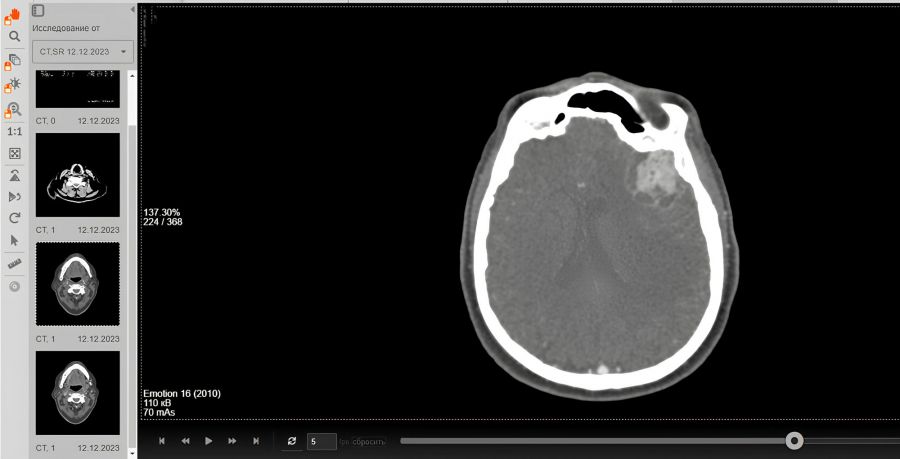

Пациентка поступила в  больницу в  тяжёлом состоянии: у  неё отсутствовала речь. Томография позволила диагностировать отёк мозга и  крупную, размером с  грецкий орех, опухоль в  зоне речевого центра коры головного мозга. В  таком состоянии человек теряет способность говорить, но  может понимать окружающих.